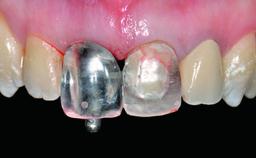

Replacement of an Ankylosed Central Incisor with a Gingival Recession: Tooth Extraction with Socket Grafting and Late Implant Placement with Simultaneous Contour Augmentation

Provisional Implant-Supported Prosthesis Prosthodontic margin > 3 mm apical to mucosal margin Prosthodontic margin > 3 mm apical to mucosal margin

Interim Prosthesis during Healing Removable Removable